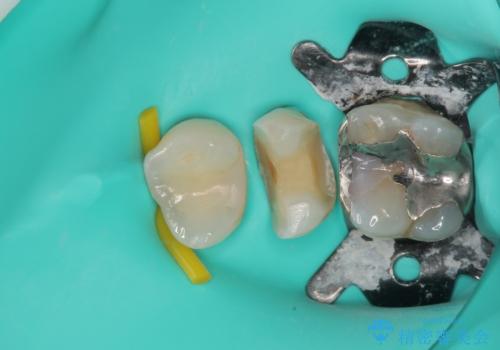

歯と歯茎の間に圧排糸と言われる糸を入れてシリコーン印象材にて精密な型どりをしました。

セラミックインレーの装着時には、唾液の侵入を防ぐために、ラバーダム防湿を行いました。